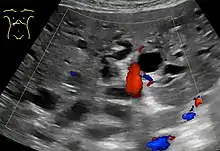

Abdominal ultrasonography (with Doppler) of dilated intrahepatic bile ducts, in this case because of pancreatic cancer. The bile ducts are colorless (black) in contrast to blood vessels (portal vein near center, and hepatic artery to the right of it) which have Doppler signal.